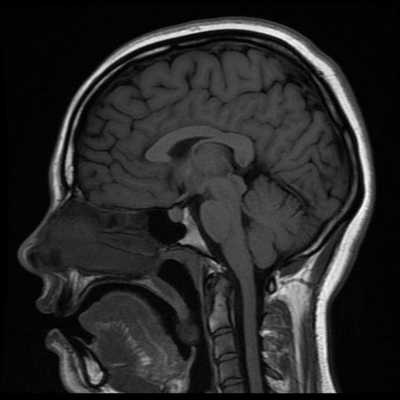

Классический пример МРТ снимков головного мозга показан на рисунках ниже. Магнитно-резонансная томография выполняется в поперечной (или аксиальной - рисунок снизу) и продольной (или сагиттальной — рисунок сверху) плоскостях.

Исследование выполняется в нескольких режимах. Основные из них Т1 и Т2. Изображения, полученные в данных режимах, часто также называют Т1-взвешенными или Т2-взвешенными снимками. Изображения, показанные выше, сделаны в Т1-режиме.